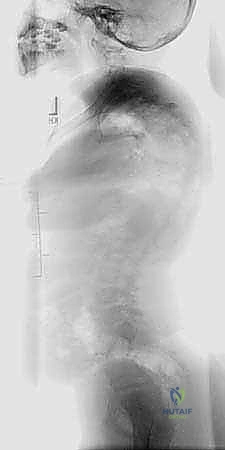

- الأشعة السينية الكاملة للعمود الفقري (Full Spine X-Rays):

- صور أمامية خلفية (AP) وجانبية (Lateral) والمريض واقف.

- يتم من خلالها قياس زاوية كوب (Cobb Angle)، وهي المعيار الذهبي لتحديد شدة الانحناء.

- أشعة الانحناء الجانبي (Side-Bending Films) وأشعة الشد (Traction Films):

- هذه الصور حاسمة جداً. يُطلب من المريض الانحناء لأقصى درجة يميناً ويساراً أثناء التصوير.

- الهدف هو تقييم "مرونة" الانحناء (Flexibility). إذا لم يتعدل الانحناء كثيراً في هذه الصور، فهذا يعني أن الانحناء "صلب" (Rigid)، وهذا هو المؤشر الرئيسي للحاجة إلى جراحة التحرير الأمامي.